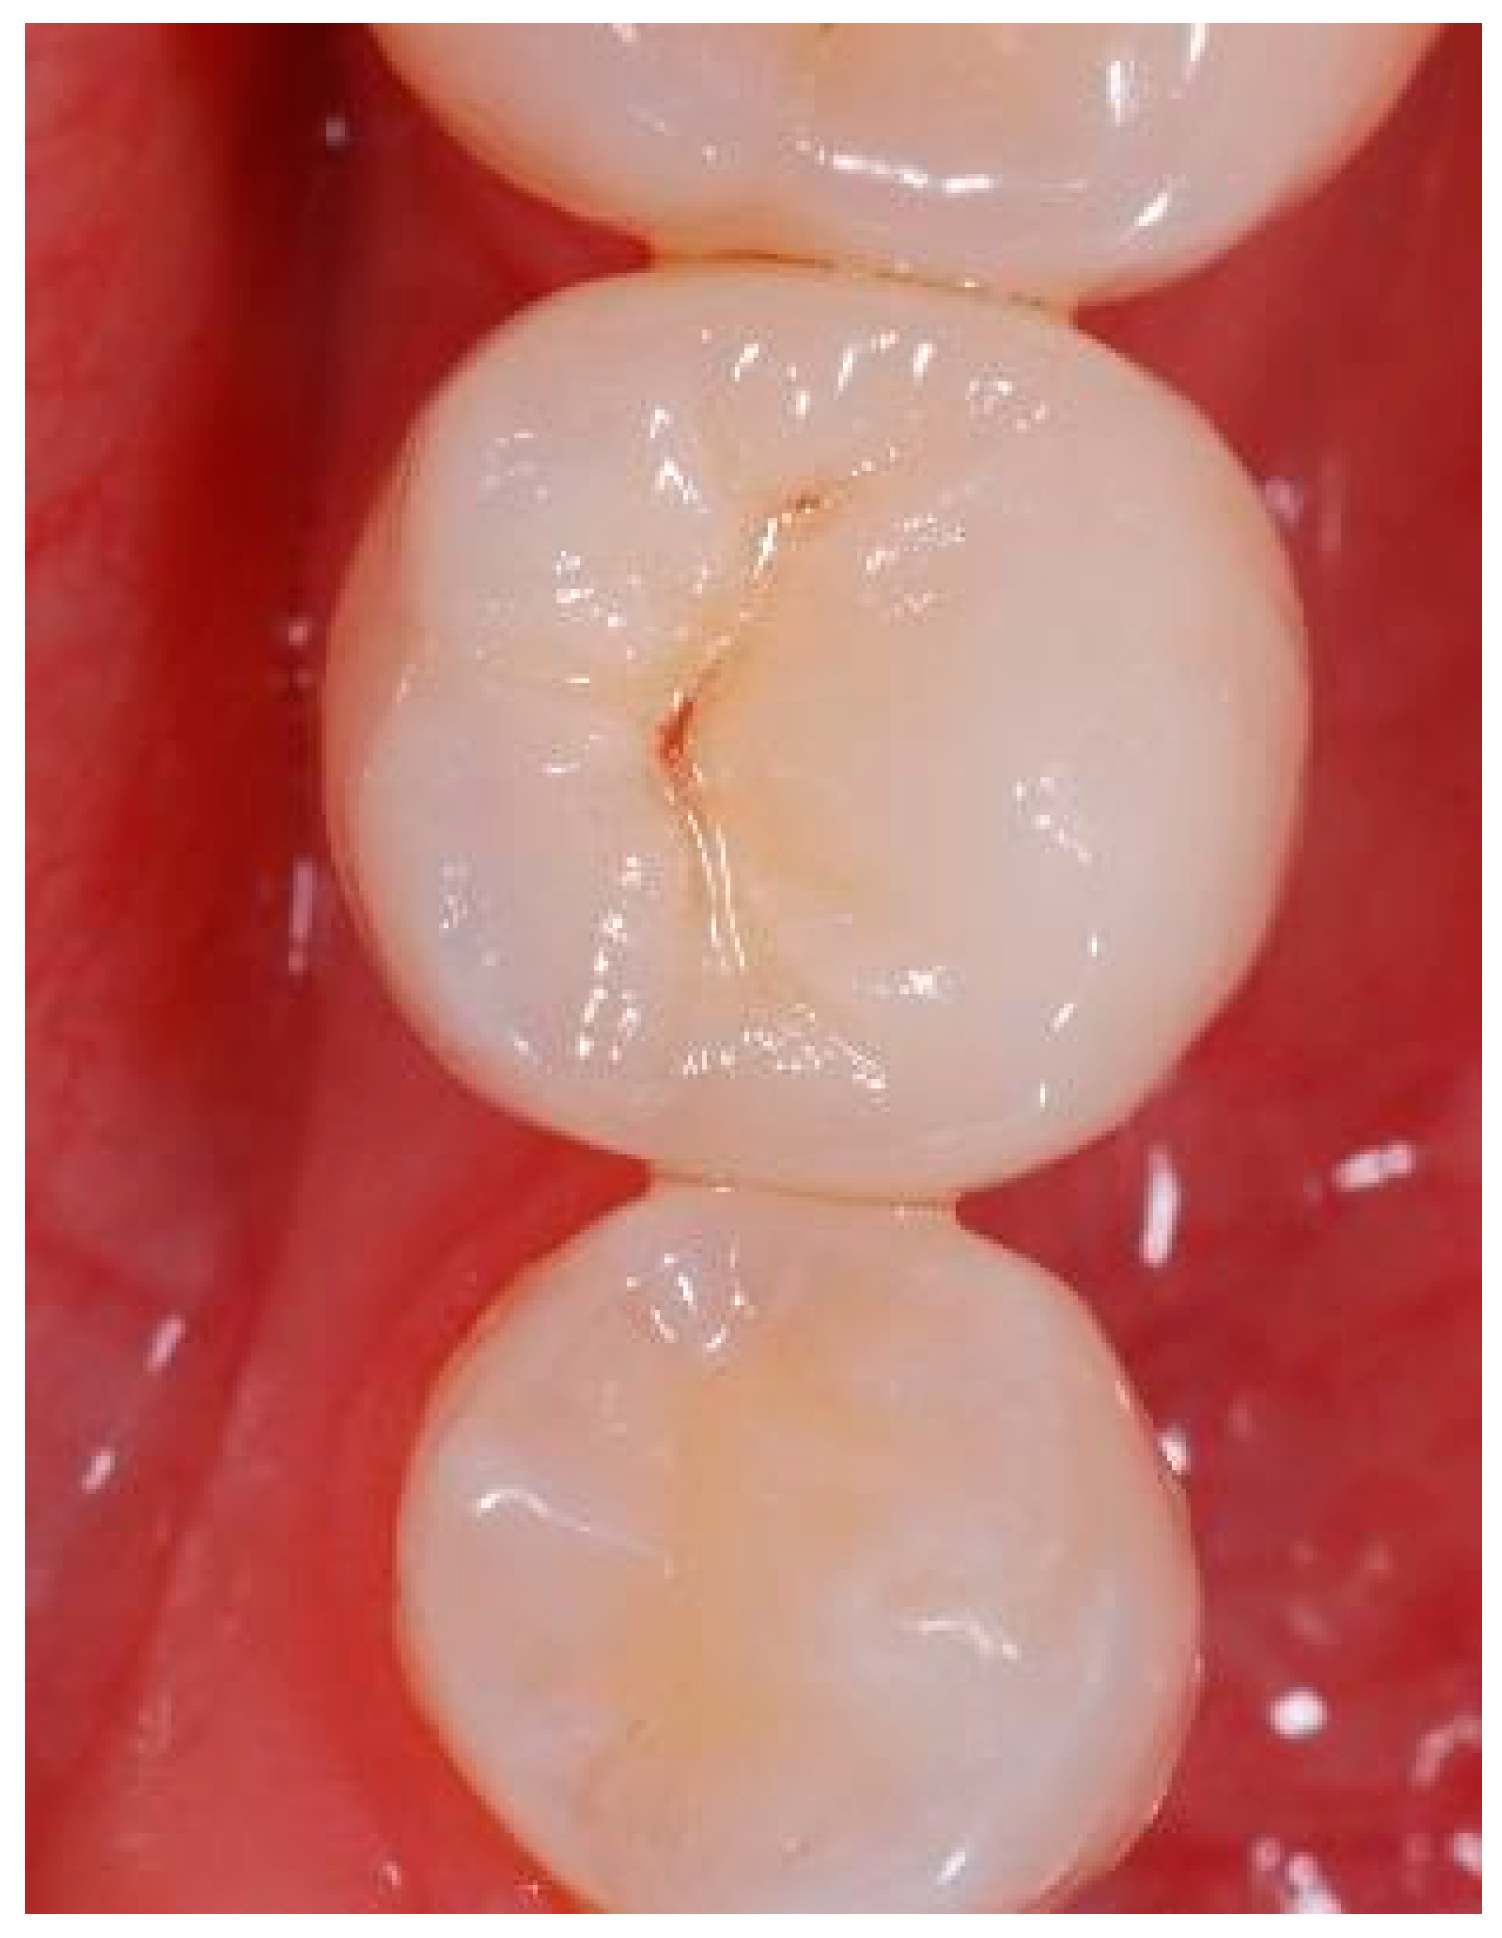

Figure A13.

Situation after crown cementation. Occlusal view.

Figure A16.

Clinical situation at the 1-year follow-up. Occlusal view.

Figure A19.

Clinical situation at the 3-year.

Figure A22.

Clinical situation at the 5-year follow-up. Occlusal view.